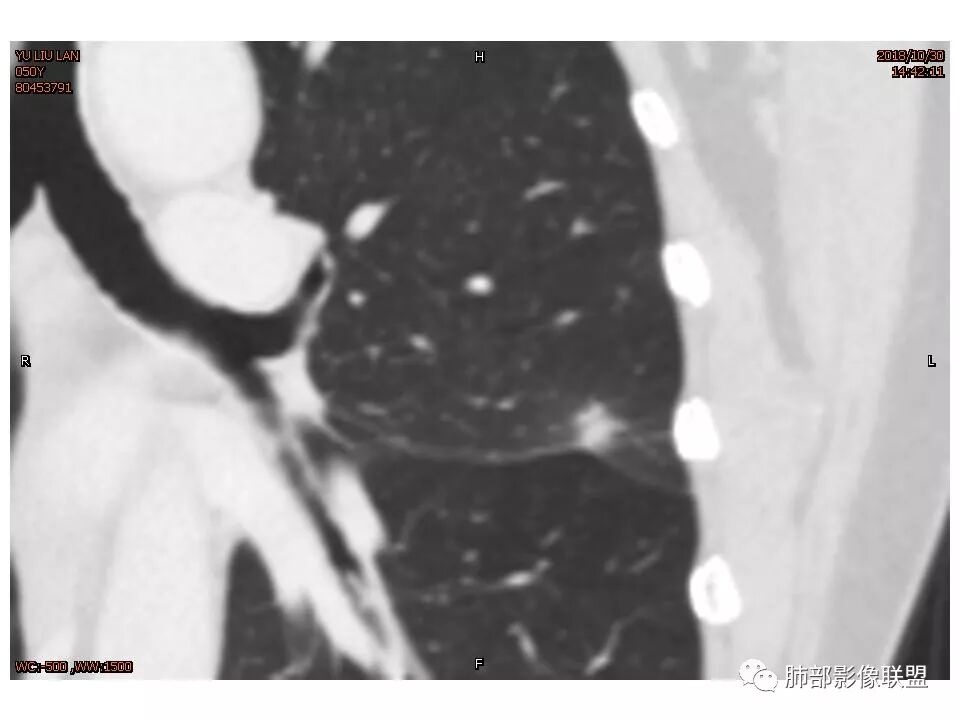

THINKER :

定位左舌,结节,有晕,晕中软毛刺,长毛刺与胸膜牵拉,收缩明显,部分呈方形,明显强化及延迟强化,有支气管近端进入远端阻塞,部分呈鬼脸

考虑:pC

鉴别:腺癌 牵拉斜裂,有动静脉相连,

处理:抗炎半月复查

结节样病灶,u型征,病灶内可见细支气管管,增强可见血管进入,略增粗,病灶周围有晕,有软毛刺,局部叶间胸膜有牵拉,考虑良性炎性病灶,抗炎后复查。

平直征、U型征、长毛刺

女性,50岁。U型凹陷、平直征

南边:支持炎性

这些层面不大放心